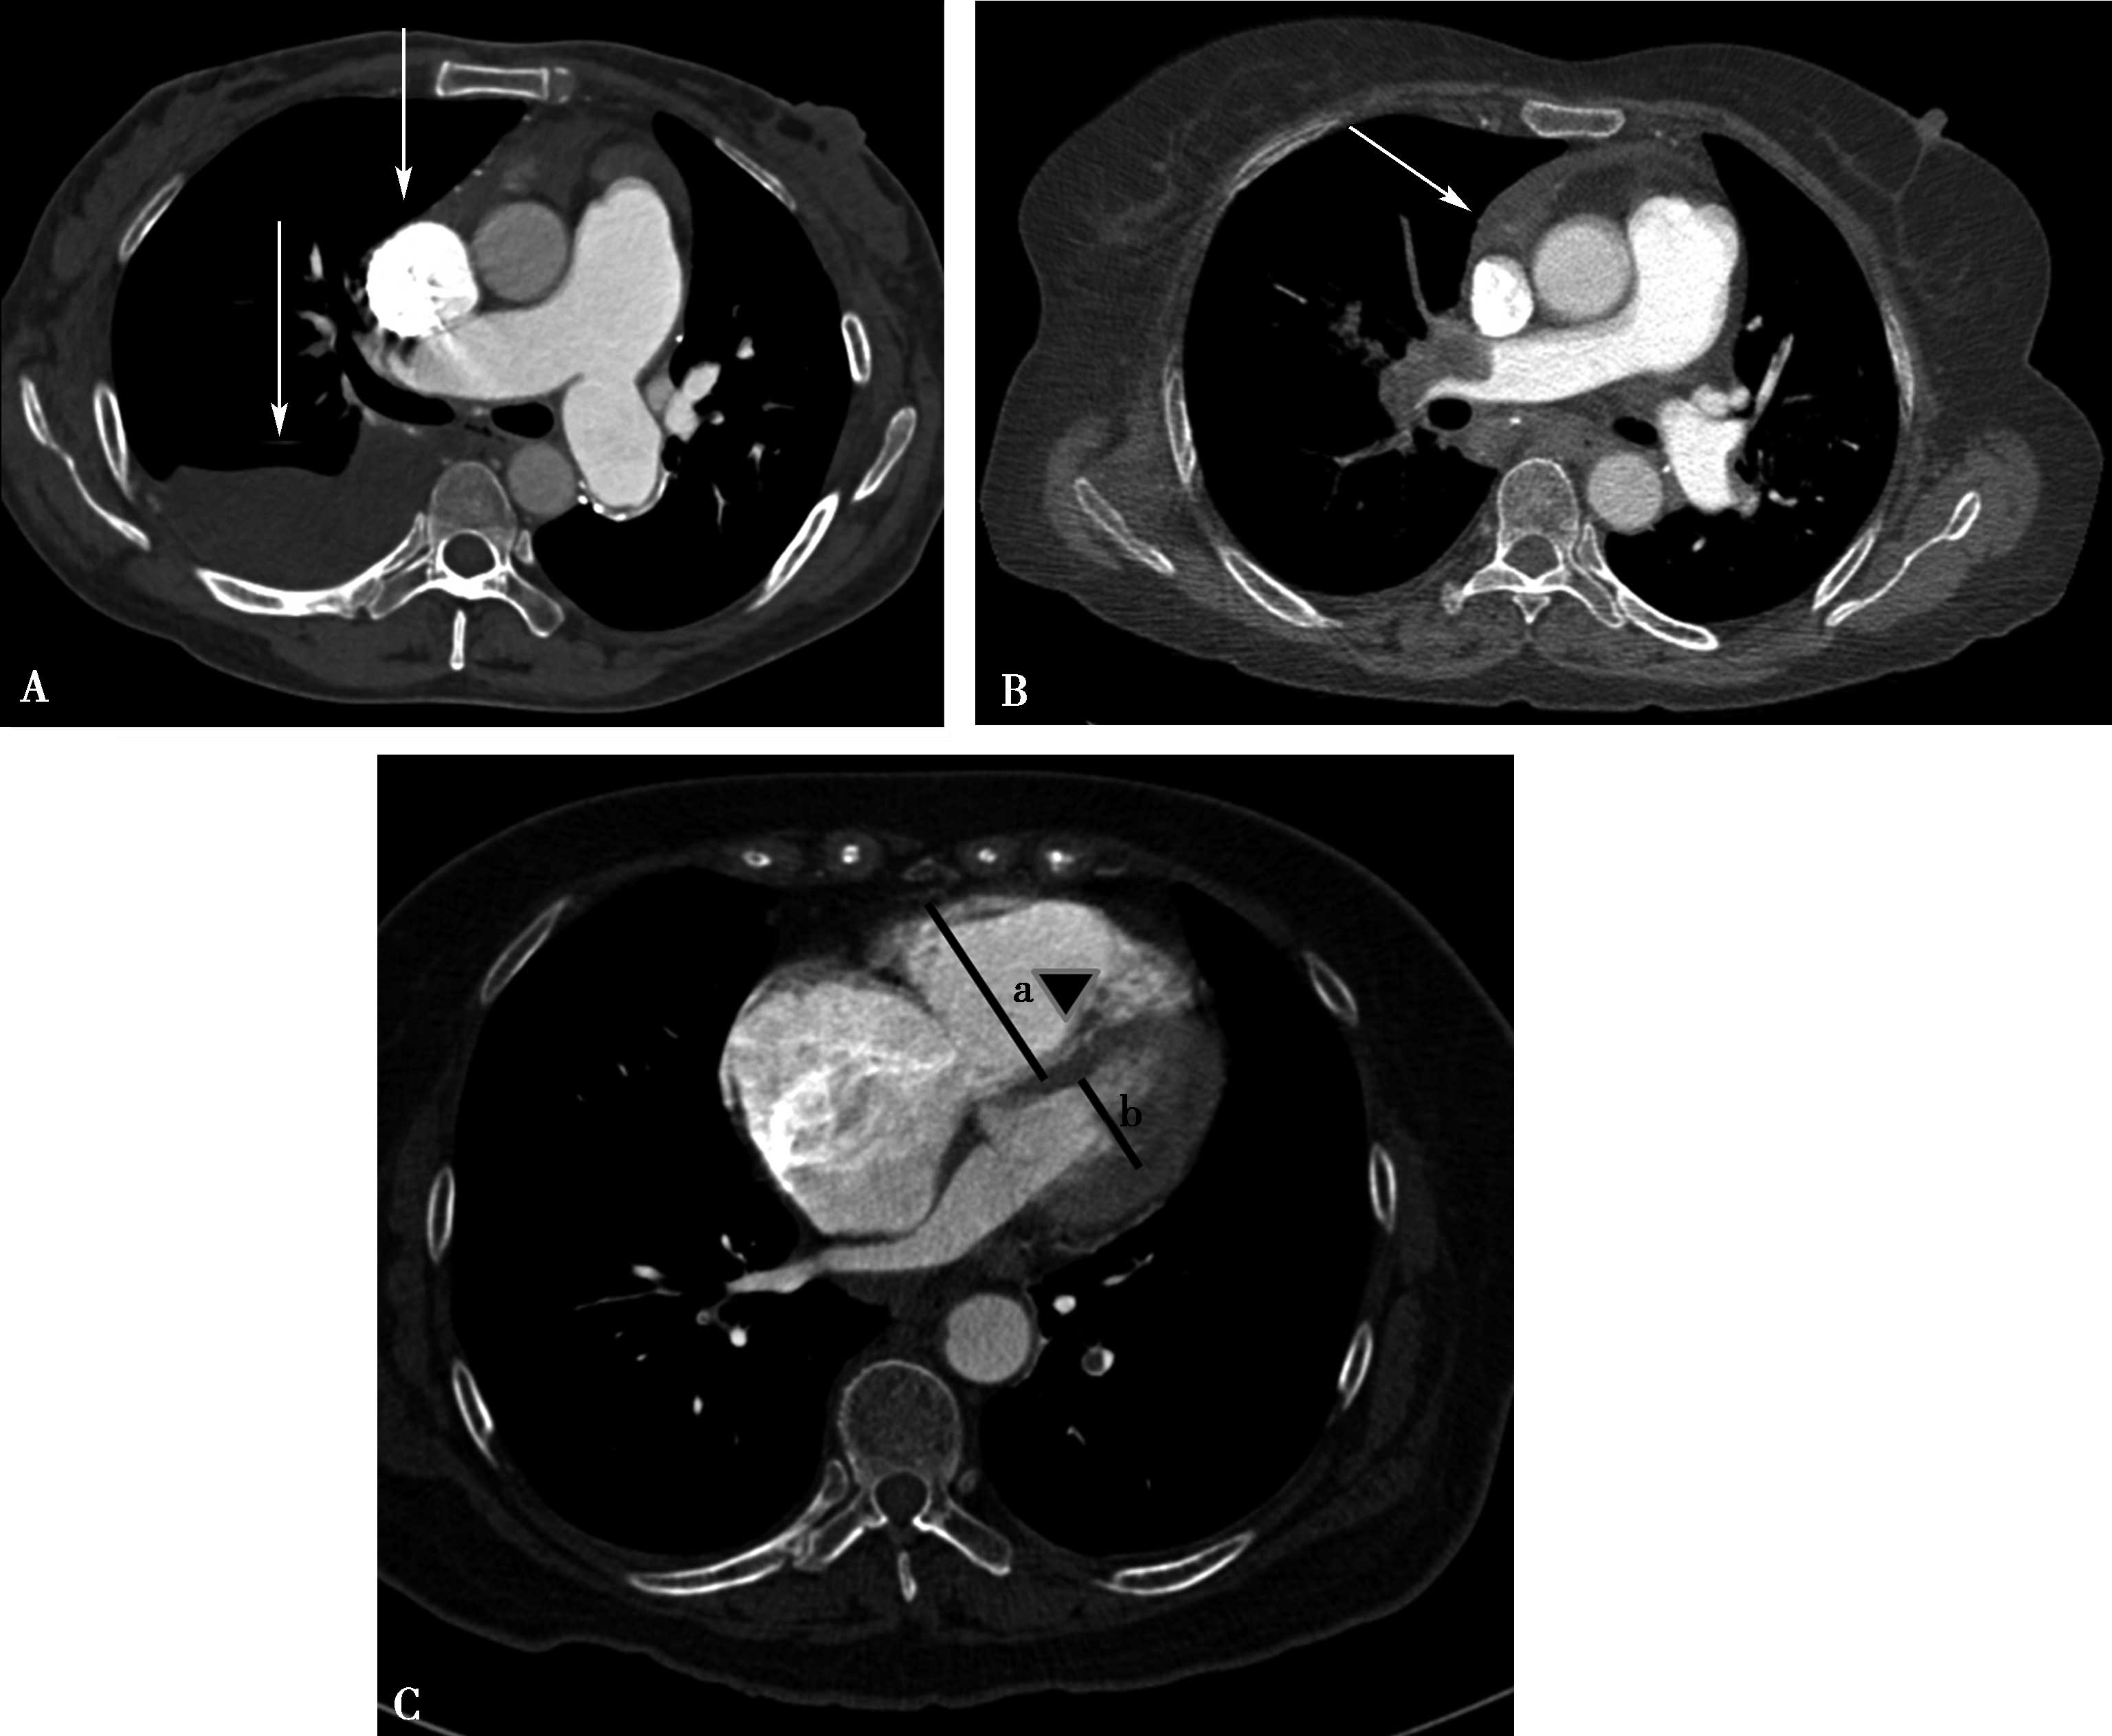

(二)双期扫描法(图8-1-5)

5.当ROI的CT值达到阈值时启动增强扫描程序。实行双期扫描,第一期为肺动脉期,从肺尖扫描至膈肌,第二期为主动脉期,由膈肌扫描至肺尖,双期扫描范围一致。双期扫描的意义在于:①充分保证了对比剂团注时间与肺动脉CT数据采集时间的吻合;②肺动脉高压或/和右心功能不全循环时延长者,是一弥补措施;③多期观察可以辨别对比剂充盈不均造成的假象;④有利于对肺灌注的评价;⑤主动脉期可以兼顾观察左心系统的病变。

图8-1-5 CTPA两期扫描应用:患者,男,37岁,二尖瓣狭窄,肺循环高压,怀疑肺栓塞。第一期右肺下叶基底段对比剂充盈不充分(ABC↑);第二期充盈充分(DEF↑),排除肺栓塞诊断